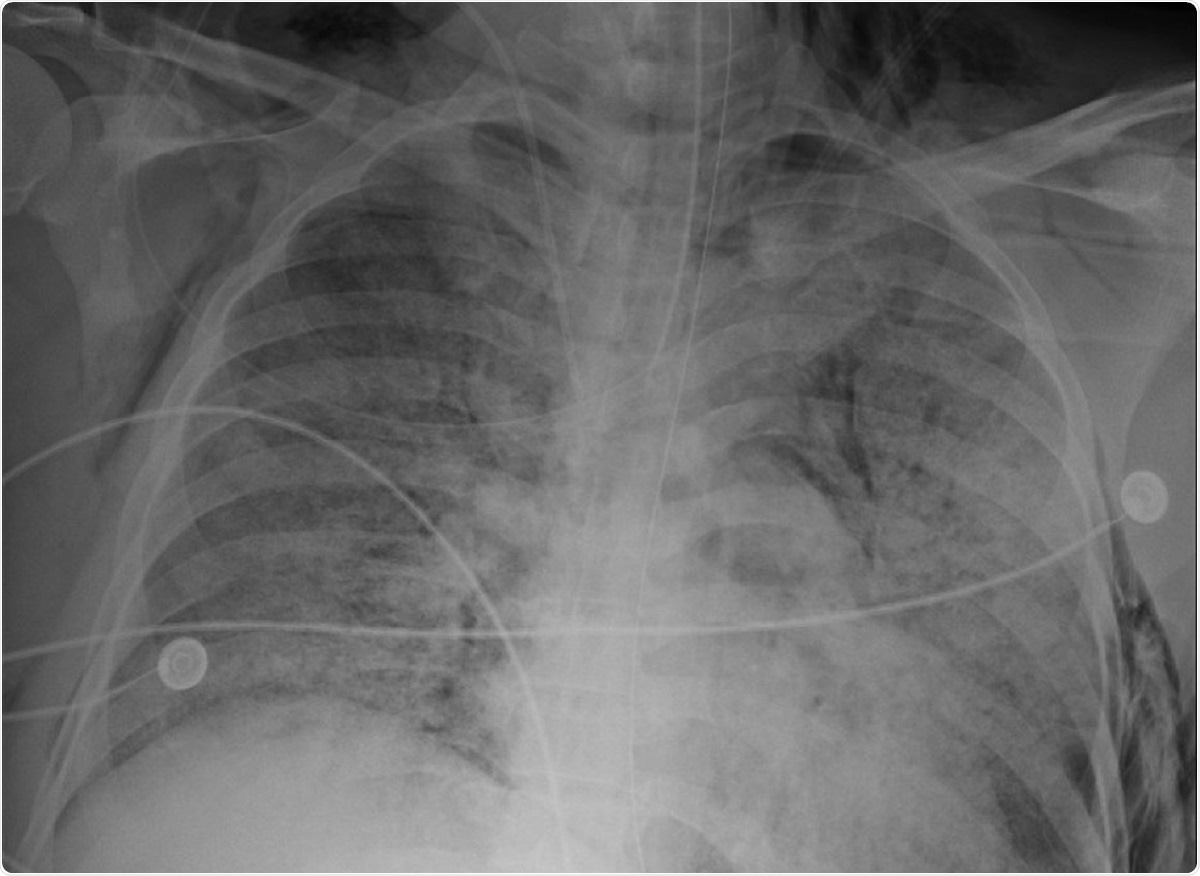

Chest radiograph showing right-sided subcutaneous emphysema and right-sided apical pneumothorax. Image Credit: original article / Cureus

Because of the presence of pneumothorax, pneumomediastinum, or subcutaneous emphysema on radiographic imaging, the patients were diagnosed with barotrauma. The total hospital length of stay for these patients ranged from 21 days to 103 days, with three of the five patients passing away due to complications related to COVID-19.